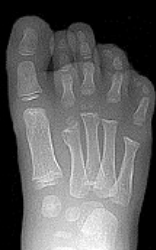

| Describe the tubulation of the metatarsals | Metatarsals are overtubulated - decreased girth. |

| Describe the tubulation of the metatarsals | Metatarsals are undertubulated - increased girth. |